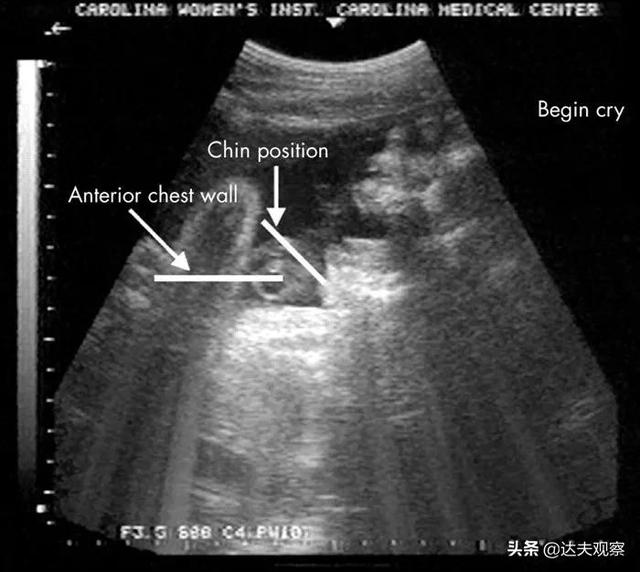

超声波技术使我们能够在胎儿还在发育时窥视子宫内部并仔细观察。例如,在《儿童疾病档案——胎儿和新生儿版》上发表的一篇视频论文中,超声波显示,一个33周大的胎儿做出了一个看起来像在哭的表情。

研究人员给胎儿施加振动和噪音刺激后,它会张开下巴,合上下巴。随着胸部的上升和头部的向后倾斜,它会不断发出三个大呼气,最后下巴会振动。10个胎儿显示了这种运动(约占所有超声波扫描胎儿的6%)。那么,胎儿在子宫里哭过吗?这取决于你如何定义哭泣。